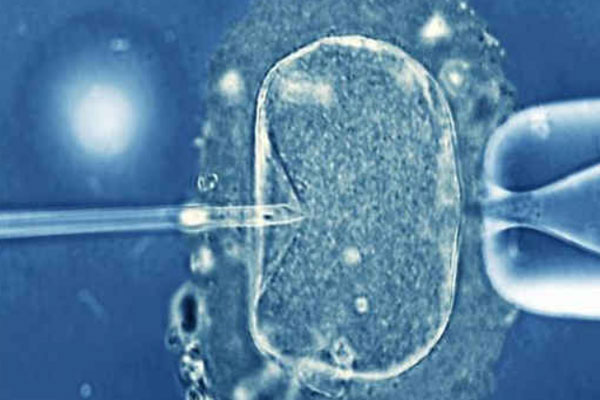

三胎政策、二胎政策的实施,现目前在生殖中心我们经常是可以看到一些30-50岁之间的女性,因为这个年龄段的自怀是没有可能了,只能通过试管进行助孕。因为女性一般过来35岁就已经算是高龄妇女了,如果说到了47岁,就已经算是超高龄妇女了,一般这个年纪的妇女想要自然怀孕的话,几率是比较低的,身体情况越复杂其几率越低。所以只能通过试管进行助孕,那么47岁的女性能不能做试管呢?成功率是多少?

答案是肯定的,47岁的人是可以进行试管婴儿技术的,但是成功率可能没有适龄生育年纪那么高。因为很多时候,随着年龄的增长,卵巢功能也会所有减退,卵子的质量、数量会下降,生育问题会面临较大的考验,有半年以上的时间不避孕不怀孕就应该积极检查,在治疗方案的选择上,医生可能也倾向于积极选择试管婴儿技术的建议,当然巧妇难为无米之炊,如果卵子不优质,胚胎质量也堪忧,试管成功率相对也会较低。

47岁做试管的成功率在20%-50%之间,如果说患者的身体情况好,卵子数量多且健康的话,其成功率可以达到50%左右,但是患者身体情况很复杂,卵巢枯竭,卵子质量不佳的话,其成功率可能不超过20%,甚至很低。高龄女性做试管的成功率一般会低于年轻女性,但这也不代表没有生育的可能,对于超过40岁的女性,则要看具体身体情况,因为做试管婴儿还是要看上面说的一些因素,这就要求女方有一个好的子宫和卵巢功能,如果都没问题的话,成功几率还是很大的哦,最重要的是,大家要努力。